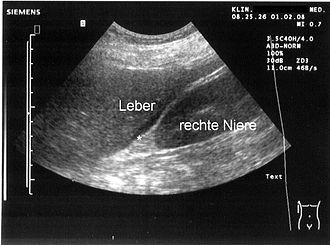

Dijagnoza uzroka počinje pretragama krvi, ultrazvukom abdomena i izravnim uklanjanjem tekućine iglom ili paracentezom (koja također može biti terapeutska). Algoritam dijagnostike bi izgledao kao što je navedeno:

- Ultrazvuk: Manja količina se ovim pregledom može vidjeti ispod jetre ili u Douglasu. G